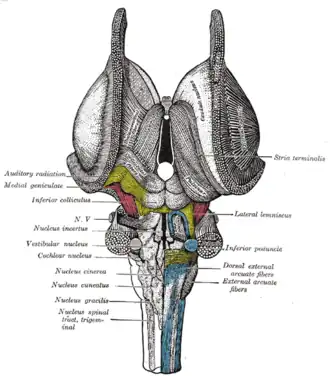

Dissection of brain-stem. Dorsal view.

Dissection of brain-stem. Dorsal view. -